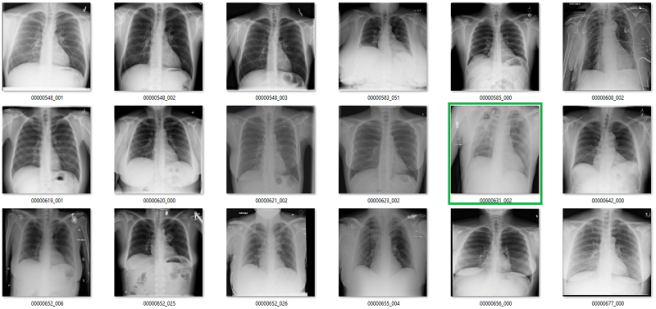

What follows is a bunch of pictures based on the labels in the dataset. In this case, they are pseudo-random. Like I said, it doesn’t have to be perfect. They are randomly chosen sequential sets of 18 images. They are not cherry-picked.

Also, I have tried to err on the side of caution, in the sense that I favour the label class when a case is equivocal.

In all the images, red = clearly wrong label. Orange = I doubt it, I wouldn’t report it, but I can’t really exclude it. Correlate clinically :p

Atelectasis

Cardiomegaly

Fibrosis

My labels aren’t perfect. Other radiologists will disagree with some of them, and the reduced resolution doesn’t help. But it should be clear that my labels and the results presented in the paper/supplement are vastly different.

I always like hard numbers, so I did my best to quantify the label accuracy where I can. I actually found it very hard to define many of the labels, which is why they are not listed below. I reviewed ~130 images in each class, and calculated the accuracy of the original labels according to my visual interpretation. This is a pretty good amount of data to use, as the 95% confidence intervals will probably be less than +/- 5%, even allowing myself up to a 20% error rate.

Visual analysis by me. Text mining results from the paper.

Again, I doubt my labels are “right” compared to some form of fairly reliable ground truth (like a panel of chest radiologists), but the difference here is stark. I think that these findings make a strong case that these labels do not appear to visually match the diseases they should represent.